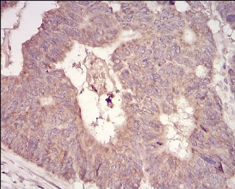

MuRF1 Mouse Monoclonal antibody[7B8E1]

This gene encodes a member of the RING zinc finger protein family found in striated muscle and iris. The product of this gene is an E3 ubiquitin ligase that localizes to the Z-line and M-line lattices of myofibrils. This protein plays an important role in the atrophy of skeletal and cardiac muscle and is required for the degradation of myosin heavy chain proteins, myosin light chain, myosin binding protein, and for muscle-type creatine kinase.

Immunogen:    Synthesized peptide of human MuRF1 (AA: 293-304).

IHC    1/200 - 1/1000